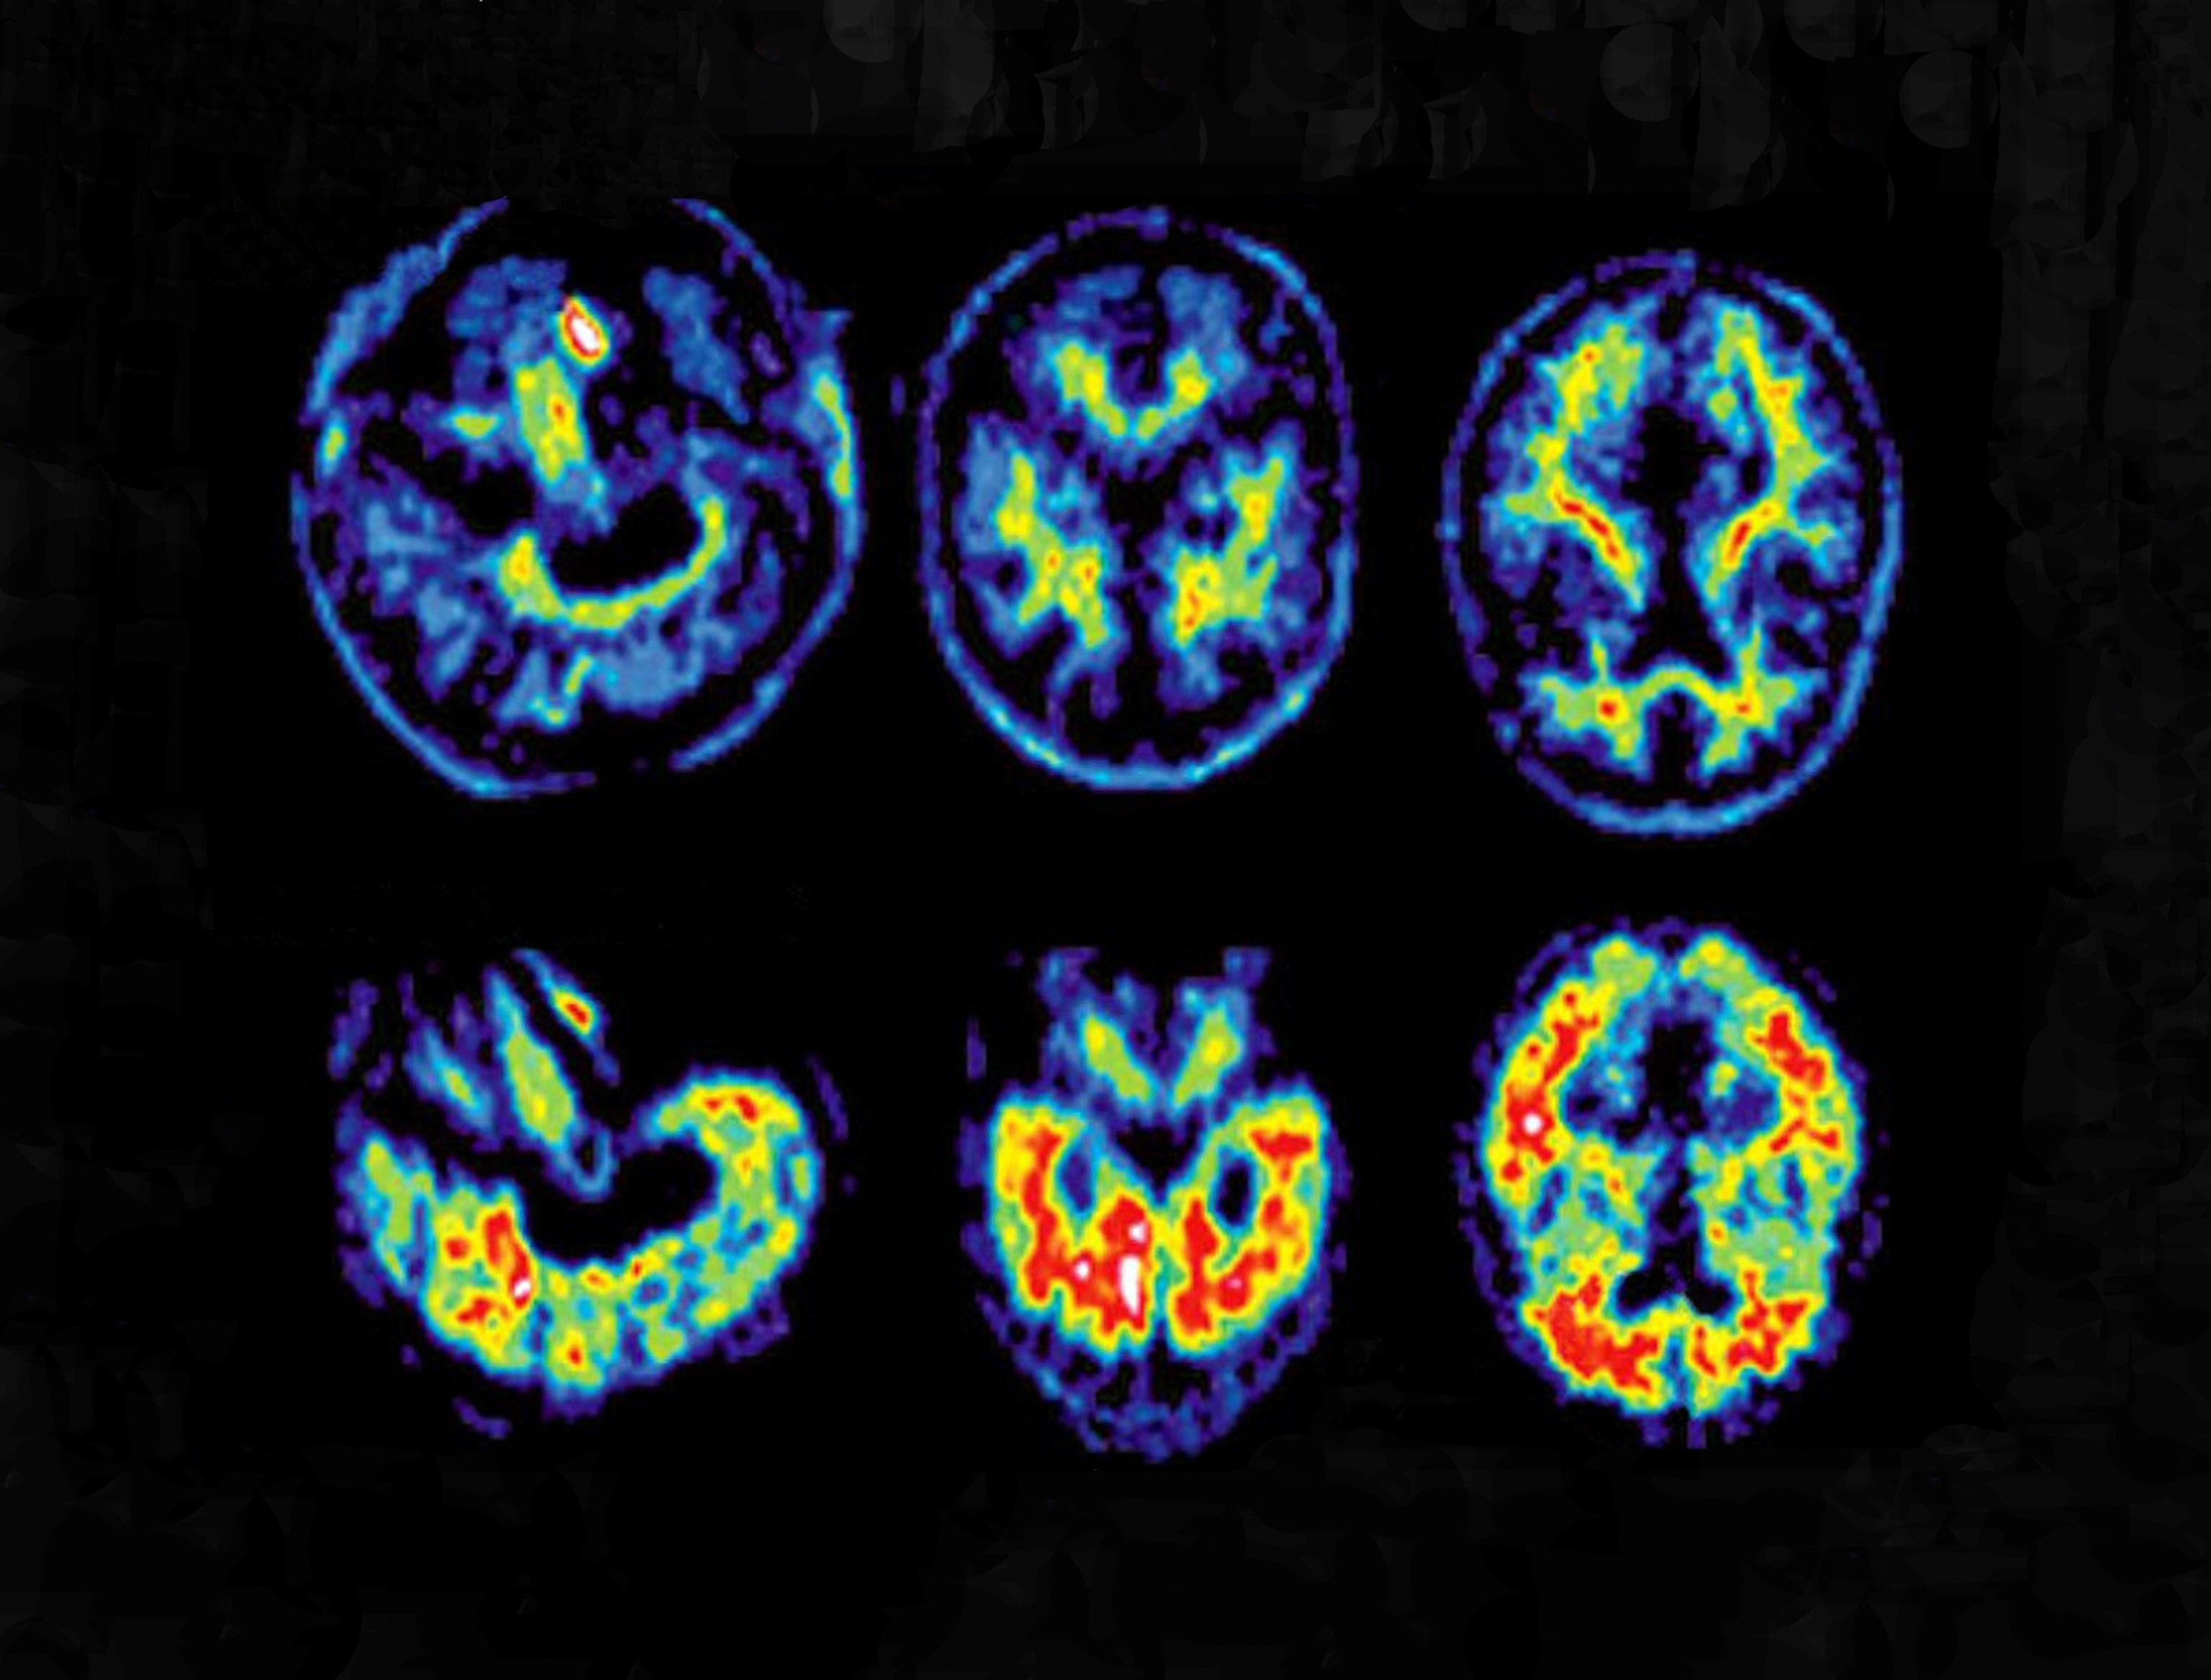

“We now understand that Alzheimer's disease begins in the brain years before a person begins to exhibit memory problems or other cognitive problems,” Grill says. Despite the lack of symptoms, their brain scans can show elevated amyloid levels. He and his colleagues are testing whether lecanemab can remove the plaques from brains of people in this pre-clinical disease stage to prevent the onset of memory problems. Participants will receive intravenous injections of the drug every two weeks for 96 weeks and then switch to every four weeks until week 216.